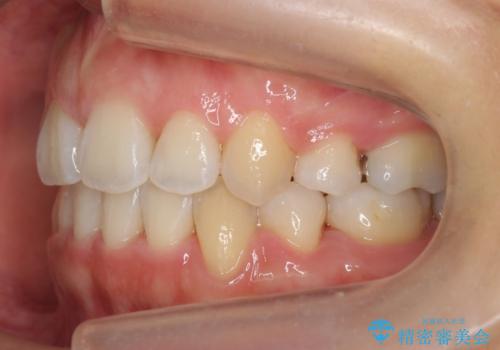

- 20代女性

- 治療計画

- 前歯のがたつきと正中のずれを主訴に来院。

小臼歯を4本抜歯しています。

ワイヤー矯正は時間はかかりますが、仕上がった後の自然な美しさは他の追随を許しません。

歯を抜いたことで、口元が下がって、横顔も理想的なラインになりました。